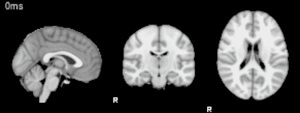

Vídeo que muestra la actividad cerebral mientras se habla.